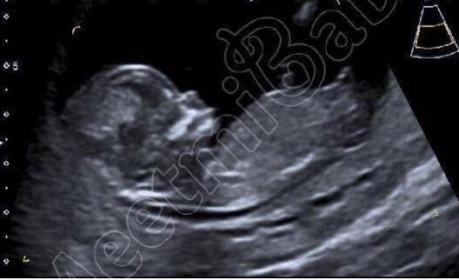

This is the picture of my friends:

Attachment 33336

Thank you so much for sharing your friend's scan pic. It's so interesting and fun to compare. Fingers crossed! :DD: